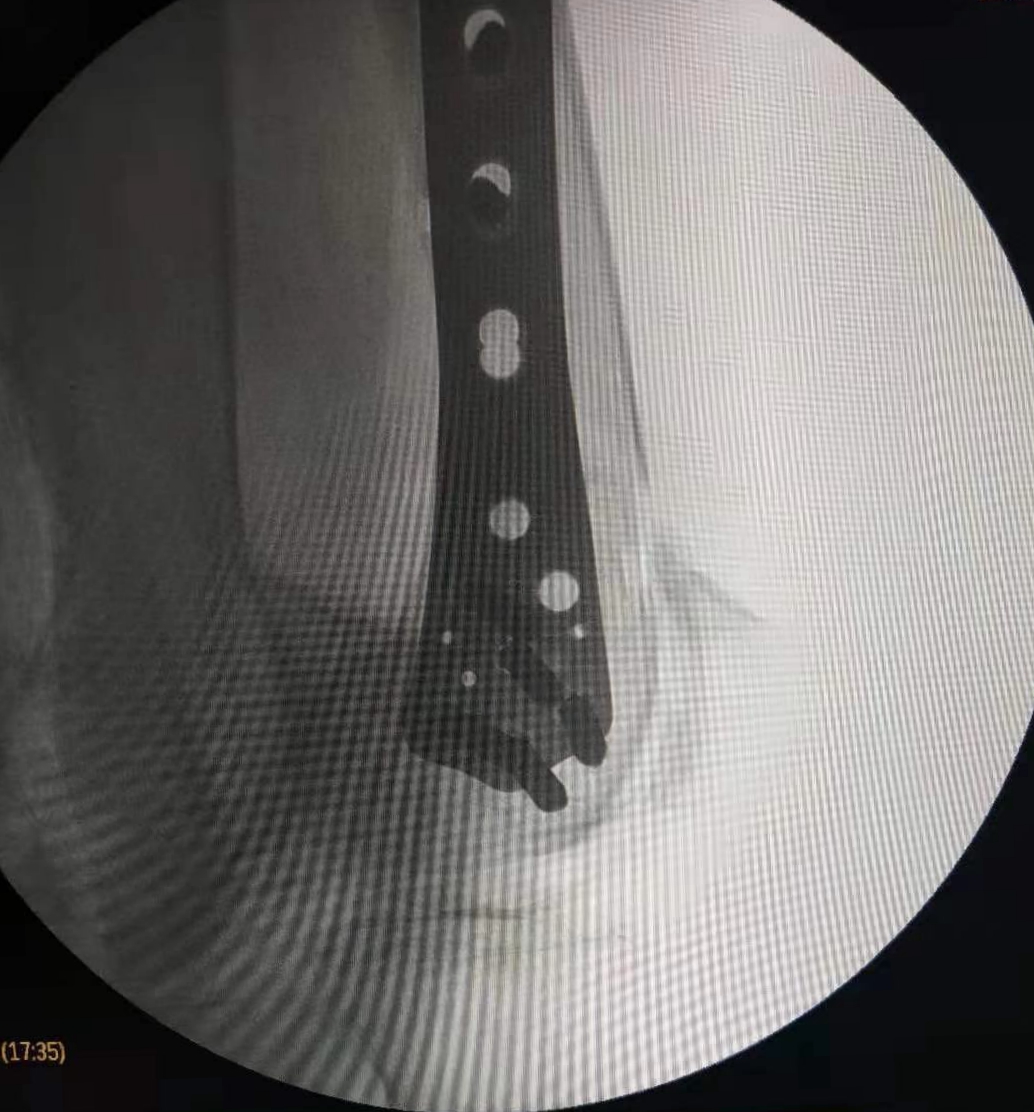

在这个寒冷的初冬,昨日市中心医院骨二科收治了一名特殊的患者,我院88岁高龄退休老专家,老人在家摔伤导致股骨髁上粉碎性骨折,拒绝去家附近的大医院,专程来我院骨二科就诊。

郭华副院长、张延平主任对病人进行了详细、全面的查体分析,因患者年龄较大,骨折严重再加上老年骨质疏松,骨折部位极易损伤后方血管,考虑患者病情的特殊性,骨二科拟行急诊手术治疗。术前,对患者进行了全面、细致的手术风险及效果评估,按照我科老年患者的优化诊疗标准流程,制定了精准的手术方案,包括风险预案、围手术期准备及护理措施,准备完成后,在急诊进行手术治疗,手术历时2小时。手术顺利、安全完成,目前患者在我科积极术后康复治疗。